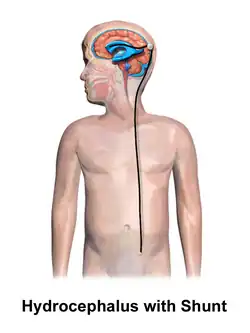

Hydrocephalus is typically treated through surgery. One option is the placement of a shunt system.[1] A procedure called an endoscopic third ventriculostomy has gained popularity in recent decades, and is an option in certain populations.[4] Outcomes are variable, but many people with shunts live normal lives.[1] However, there are many potential complications, including infection or breakage.[4] There is a high risk of shunt failure in children especially.[4] However, without treatment, permanent disability or death may occur.[1]

Hydrocephalus is treated through surgery by creating a way for the excess fluid to drain away. An external ventricular drain (EVD), also known as an extraventricular drain or ventriculostomy, provides relief in the short term.[48] In the long term, some people will need any of the various types of cerebral shunts.[48] It involves the placement of a ventricular catheter (a tube made of silastic) into the cerebral ventricles. This creates a way to bypass the flow obstruction/malfunctioning arachnoidal granulations. The excess fluid drains into other body cavities where it can be resorbed. Most shunts drain the fluid into the peritoneal cavity (ventriculoperitoneal shunt).[49] Other shunts drain the fluid into the right atrium (ventriculoatrial shunt), pleural cavity (ventriculopleural shunt), and gallbladder.[49]

A shunt system can also be placed in the lumbar space of the spine. This allows the excess fluid to be redirected to the peritoneal cavity (lumbar-peritoneal shunt).[50] Another treatment for obstructive hydrocephalus is an endoscopic third ventriculostomy (ETV). This surgery creates an opening in the floor of the third ventricle so that CSF flows directly to the basal cisterns. This treatment can shortcut any obstruction like aqueductal stenosis. This may or may not be appropriate based on individual anatomy. Some infants can be treated with ETV and choroid plexus cauterization.[51][52] Choroid plexus cauterization reduces the amount of cerebrospinal fluid produced by the brain. The technique, known as ETV/CPC, was pioneered in Uganda by neurosurgeon Benjamin Warf and is now in use in several U.S. hospitals.[51][52]